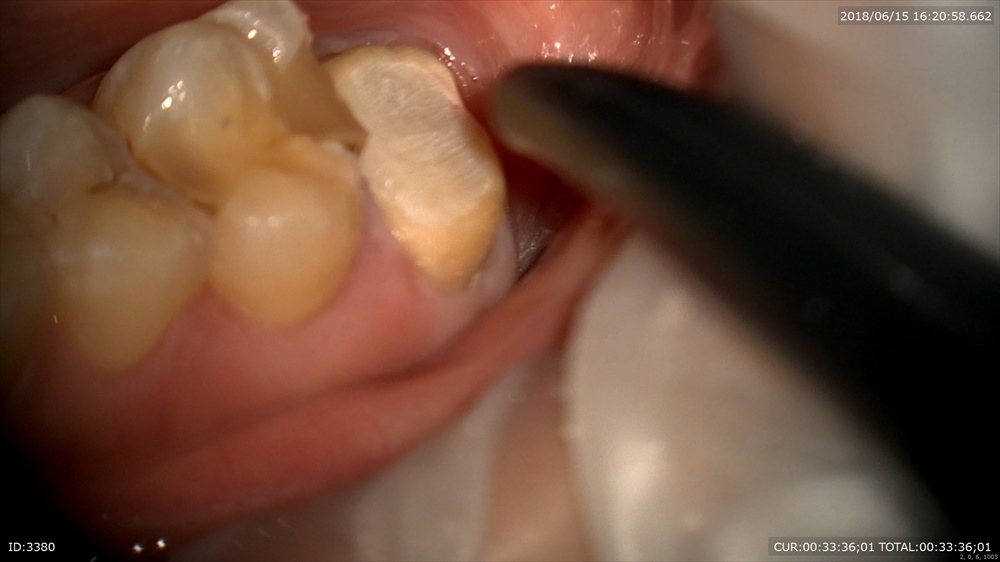

ですので本日土台と仮歯を入れました。

土台。

仮歯

セット

今日から噛めるので楽しみと喜んで帰られました。Hさんから